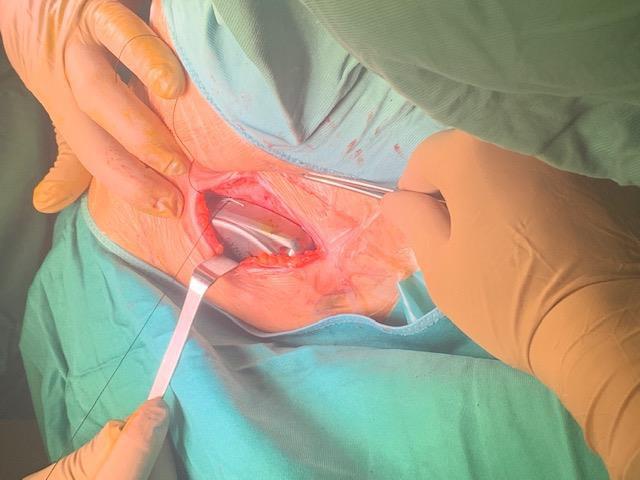

Adductor Longus L2, L3

Vastus Lateralis L3,L4

Tibialis Anterior L4, L5

Peroneus longus L5, S1

Gastrocnemius S1, S2

Abductor hallucis S1, S2

Sphincter S2